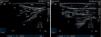

Results and conclusionsThe ultrasound sequence to perform this block is shown, together with simple X-ray dye images and gadolinium MRI images to understand the spread and pathways that can explain the benefit of this novel approach.

Resultados y conclusionesMostraremos la secuencia ecográfica para poder realizar este bloqueo junto con imágenes con contraste radiográfico y resonancia magnética con gadolinium para poder entender los beneficios de este bloqueo.